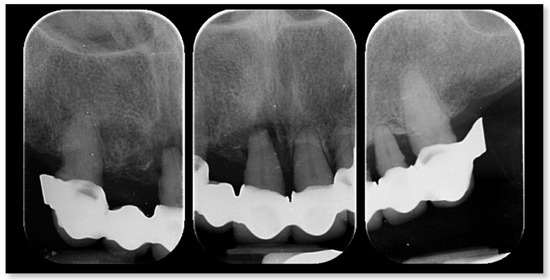

- Accuracy was tested by means of direct vision and tactile sensation, performed by applying alternately pressure on the aluminum try-in, and then the definitive metal framework (Alternate Pressure Technique), secured without screws, to determine if any movement occurs. In addition, the one-screw test proposed by Jemt and co-workers was performed in case of doubts occurred [11]. No discrepancy of the radiopaque, aluminum try-in, secured with only one screw tightened, was observed [11]. Peri-apical radiographs were taken if needed. The same operator (MT) performed both tests using a microscope magnification (10× to 16×);